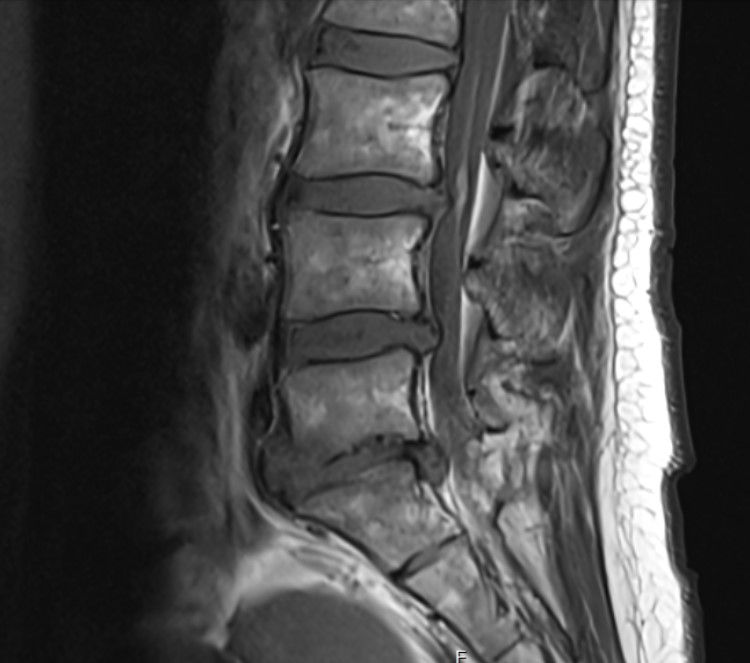

mri 상태가 그렇게 안좋은가요??ㅜㅜ

통증은 크게 없는데 상태가 심하게 안좋다고 하는데

• 1번 째 사진

MRI 상에는 디스크가 일정 부분 돌출되어있어 심해보이긴 합니다. 하지만 저희 몸이라는게 꼭 디스크가 돌출되었다가 모든 사람이 아픈것은 아닙니다. 정말 통증이라는 부분은 뇌에서 느끼고 반응하는 것이기 때문에 사람마다 다를 수 있습니다. 저렇게 되어도 통증이 없으면 일상생활 하셔도 됩니다. 하지만, MRI까지 찍으신거 보면 허리가 뭔가 문제가 있으니까 찍으신거같은데, 현재 영상자료로도 심해보이긴하여서 걷기 정도 하시는게 좋을거 같습니다. 그리고 걷기도 만보 보다는 처음에는 2~3천보에서 시작해서 점점 늘리시는게 좋을것으로 보입니다. 부디 잘 회복되시길 바라겠습니다. 감사합니다.

허리 디스크가 돌출 혹은 파열이 발생하여 주변의 신경을 압박하거나 염증이 발생하는 상태로 보여지는데요, 가벼운 산책과 같은 운동은 크게 건강에 악영향을 주지는 않습니다. 그러나, 갑작스럽게 만보정도 걷게 되는 경우에는 운동량 증가에 의해서 불편감이나 통증이 발생할 수 있기 때문에, 적절한 운동량부터 시작해보시는 것이 좋겠습니다. 또한, 코어근력을 증가시켜 척추의 안정화를 위해 데드버그나 버드독과 같은 기초적인 코어운동을 해보시는 방법도 고려해보시는 것을 추천드리겠습니다.

디스크가 심한 편이기는 하네요

요추 디스크가 밀려나와 신경을 자극하는 양상으로 저림증이나 통증이 생길 수 있겠습니다.